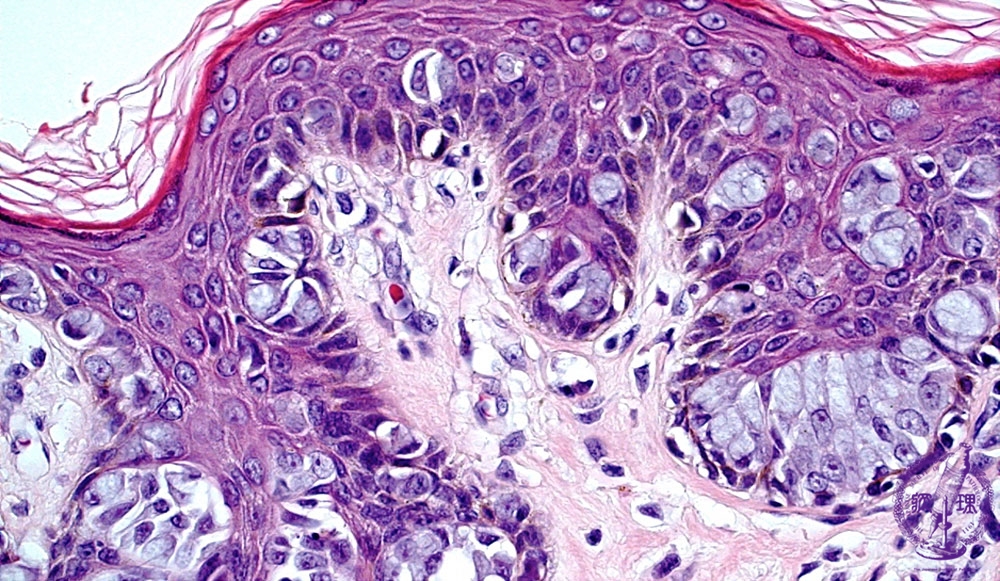

- 14.Breast

- (9)Paget’s disease

Microscopic image(HE stain, high power view):Paget cells can be detected in the full thickness of the skin, but with a strong tendancy to stay within the epidermis. The large nuclei of Paget cells with prominent nucleoli, often pushed aside by intracellular mucous.